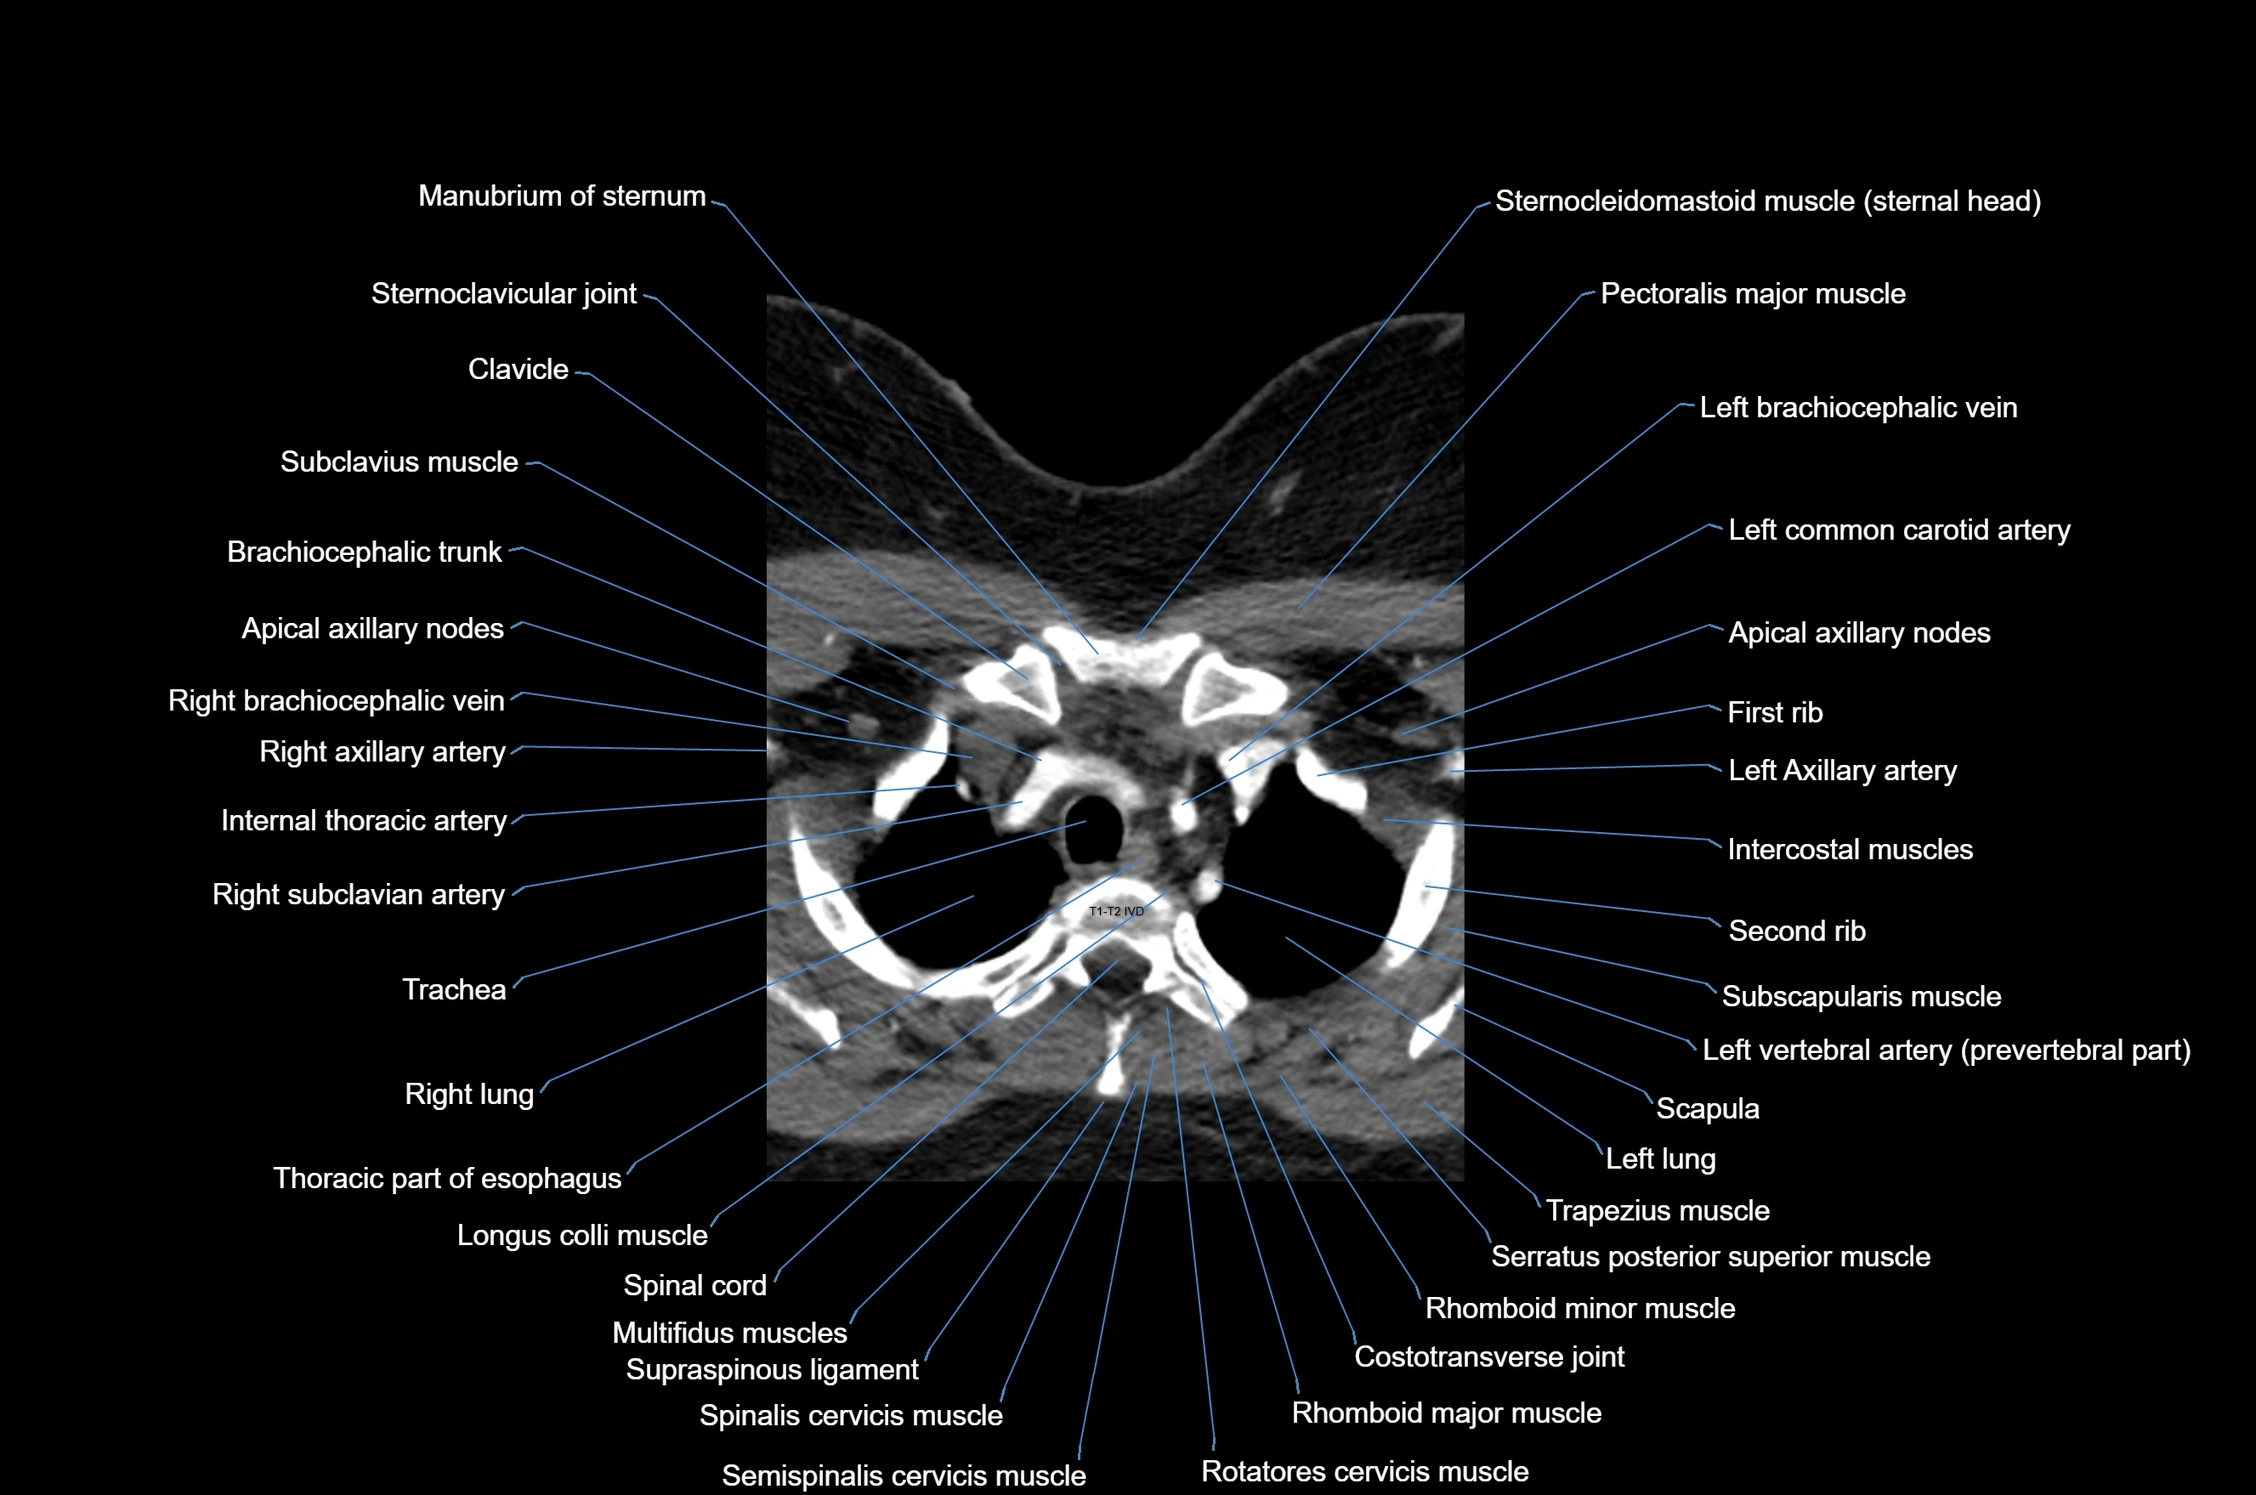

- Axillary artery

- Brachiocephalic trunk

- Clavicle

- Costal notches

- Costotransverse joint

- First rib

- Intercostal muscles

- Internal thoracic artery

- Left brachiocephalic vein

- Left common carotid artery

- Left subclavian artery

- Levator scapulae muscle

- Longus colli muscle

- Multifidus muscles

- Pectoralis major muscle

- Rhomboid major muscle

- Rhomboid minor muscle

- Rotatores cervicis muscle

- Semispinalis cervicis muscle

- Serratus anterior muscle

- Serratus posterior superior muscle

- Spinal cord

- Spinalis cervicis muscle

- Subclavius muscle

- Supraspinous ligament

- Thoracic part of esophagus

- Trachea

- Trapezius muscle